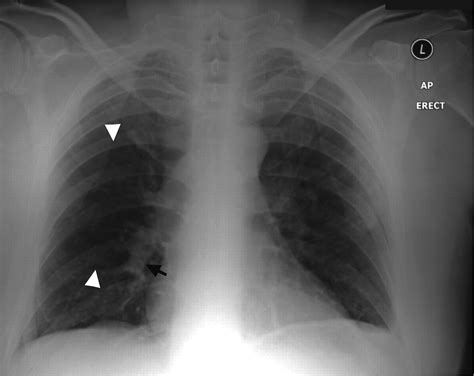

Diagnosing a Pulmonary Embolism

Diagnosing a pulmonary embolism involves a combination of medical history, physical examination, and diagnostic tests. The diagnostic process typically includes:

• Computed tomography pulmonary angiography (CTPA): This is a type of CT scan that uses contrast dye to visualize the pulmonary arteries and detect any blockages.